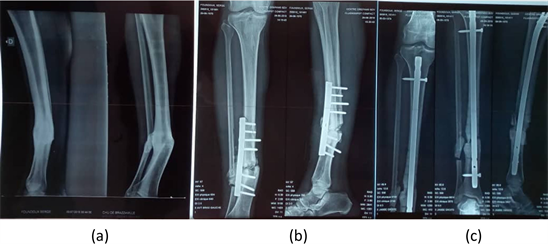

From an anatomical point of view, the reduction was anatomic in 3 patients operated by locked nail and non anatomical in 2 patients operated by screwed plate of which one underwent an early reoperation with replacement of the plate by an intramedullary nail with a distal locking screw (Figures 1(a)-(c)). We then observed at 3 months of recovery, a secondary angulation on intramedullary nail.

Figure 1. (a) X-ray of the leg before the operation; (b) Non anatomical alignment managed by screwed plate; (c) Early reoperation with replacement of the screwed plate by an intramedullary nail.